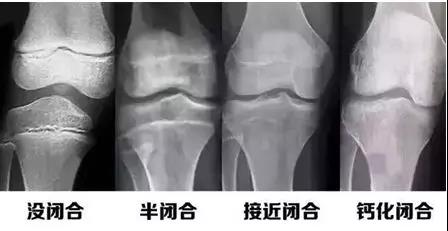

人的生長發(fā)育的程度可以用兩個年齡來表示,即生活年齡(日歷年齡)和生物年齡(骨齡)。

而骨齡和兒童身高之間有著密切的關(guān)系,通過骨齡可以及早了解兒童的生長發(fā)育潛能以及性成熟的趨勢,還可預(yù)測兒童的成年身高。